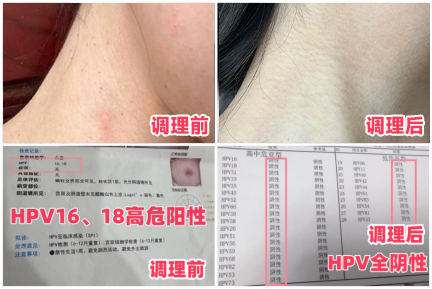

万万没想到的是,就是这个【抗HPV三联疗法】,前后调理3个周期,彻底帮我摆脱HPV高危病毒感染,拿到全阴的检查结果后,我激动在医院走廊里放声大哭。

亲眼看到全部转阴报告单,我惊讶不已!赶紧再次联系老师,表达感谢的同时,也向【抗HPV三联疗法】老师了解具体的调理步骤,分享给大家!可以加老师微信号17753103098☞查看二维码添加可以免费领取方案, 老师一定会帮大家解决的。